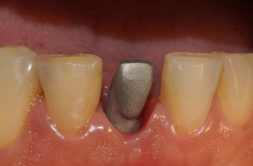

Após sete dias da moldagem, foi realizada a prova do coping em boca, para verificar a boa adaptação, fixação e a seleção da cor. Após isso, o provisório voltou a ser instalado (Figura 21).